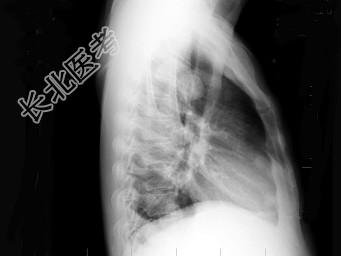

- 单项选择题男,38岁, 咳嗽、胸痛、咯血1天,X线检查如图, 最可能的诊断是 ( )